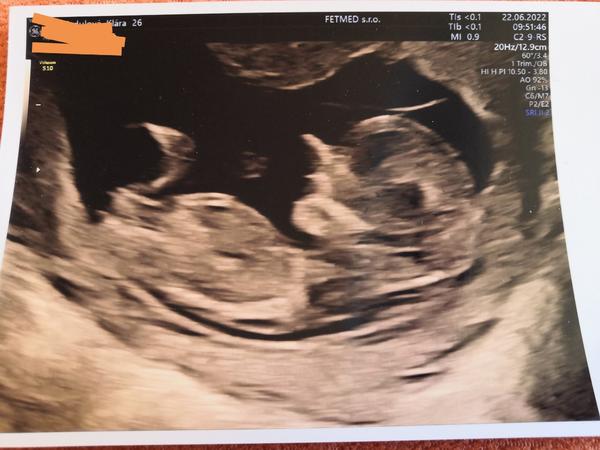

Tak mi už 4.doktorka řekla že to vypadá na holčičku. Dnes jdu na kontrolu, jsem v 16.týdnu,tak snad už to půjde zjistit s větší jistotou.☺️

@klarrrinka holka